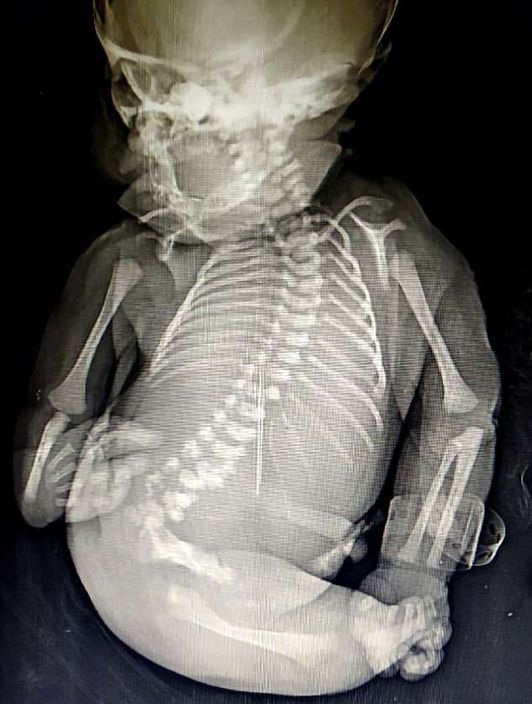

「美人魚」寶寶雙腳相連僅活15分鐘。網上圖片

由於Disksha在懷孕期間沒有積極產檢,僅在懷孕8個月時進行一次超音波檢查,所以不了解嬰兒的狀況。該BB雙腳骨骼發育不全且連在一起,看起來似是美人魚的魚尾,加上缺少性器官,醫生無法判定性別。

寶寶不但雙腿有缺陷,腎和肺部等器官也有畸形問題。網上圖片

該名嬰兒並非「美人魚」,而是患上「天生併腿畸形(Sirenomelia)」,又稱「美人魚綜合症(Mermaid Syndrome)」,是一種非常罕見的先天性缺陷,每6萬至10萬新生兒中會有一例,而且死亡率極高,約一半會胎死腹中。就算能順利出生,幾乎全都在出生後一至兩天內死亡。